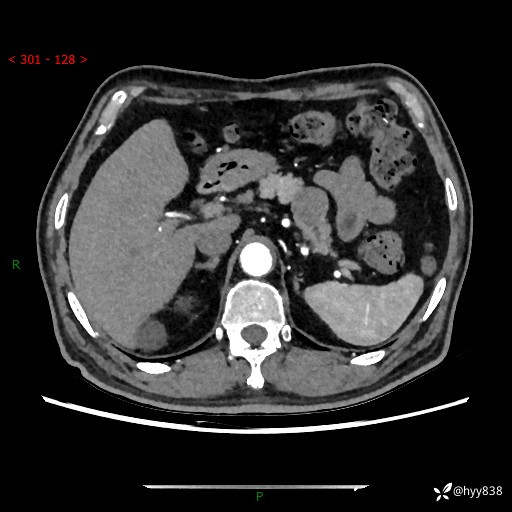

【检查】:胰腺CT平扫+增强